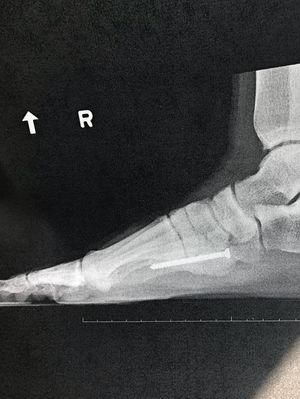

5th metatarsal repair surgery, 4 months post op

A follow up to a previously posted surgery, which can be seen, along with other X-ray angles on my profile